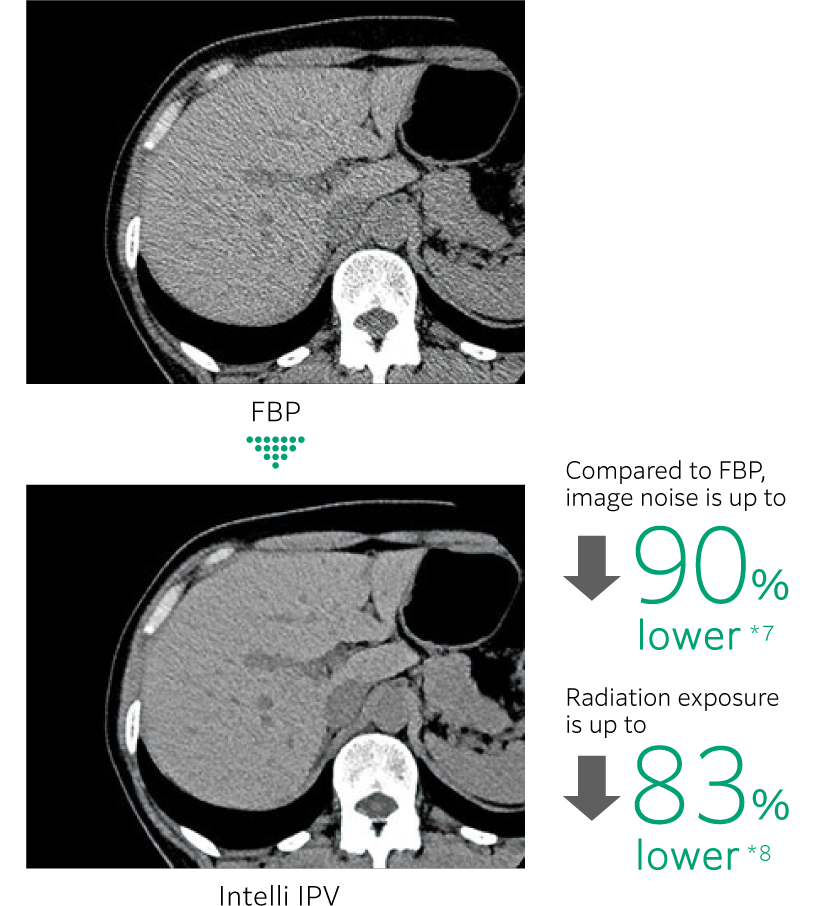

Intelli IPV 是一種利用 AI 技術開發的影像重建技術。透過使用大量經過充分疊代處理的影像作為訓練資料,實現高速且高精度的影像處理,根據富士軟片的視覺模型,使用原始資料的重建處理讓 NPS(雜訊功率頻譜)更接近 FBP(濾波反向投影),即使在高雜訊降低率下也能保持影像紋理, 可實現最高 90% 的影像雜訊*7,以及最高 83%*8的的輻射劑量減少。在低對比檢出能力方面更達到傳統影像處理的 2 倍效果。*8

同時減少輻射暴露和提高可見性

- *6 Intelli IPV 運用 AI 技術中的機器學習所開發。系統效能與準確性不會隨使用次數自動變化。

- *7 相較於 FBP 其使用 Intelli IPV 強度等級 Strong5 進行測量,並對水假體進行測試。根據臨床任務、病患體型、解剖部位及檢查內容,實際成效可能有所差異。

- *8 相較於 FBP,其使用 Intelli IPV 強度等級 Strong5 以 0.625 毫米的切片厚度進行測量,並使用模型觀測器方法結果,根據 MITA CT IQ 假體 CCT189 假體實驗室進行測試。根據臨床任務、病患體型、解剖位置和臨床檢查,獲得的效果可能較小。